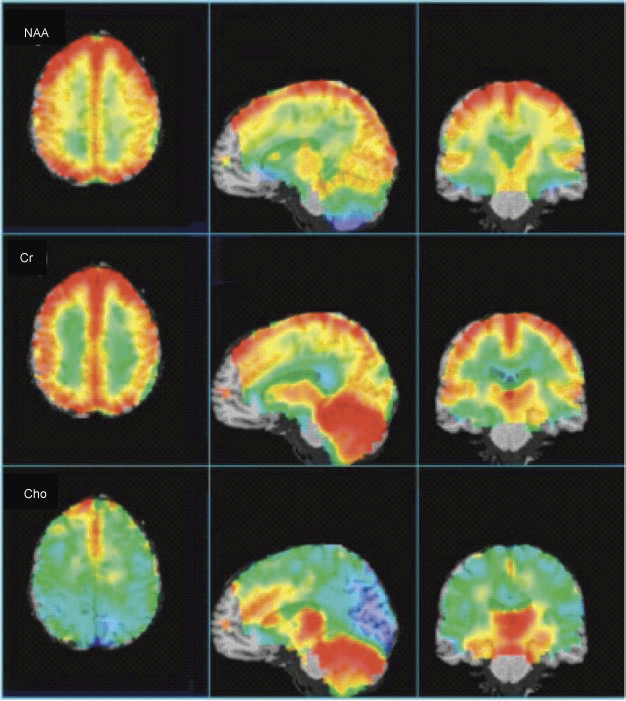

Figure-1 shows the average results from a 1.5 T whole brain EPSI

study (14 subjects, age range 27–48 (average 36)), recorded at

TE 70 msec. At the level of the lateral ventricles and above,

brain spectra show fairly characteristic patterns for gray and

white matter, although there are some anterior–posterior

differences, in particular with higher Cho in frontal brain

regions. Depending on the quantification technique used (and if

partial volume correction for CSF is applied or not), most

studies have found that the Cho is higher in white matter than

cortical gray matter, while Cr levels are lower in white matter

than gray matter. NAA levels (if measured without CSF

correction) are typically quite similar between gray and white

matter, but since cortical gray matter voxels typically have

more CSF contamination than white matter voxels, after CSF

correction, gray matter NAA concentrations are usually higher

than white matter. At the level of the third ventricle and

below, significant anatomical variations exist in brain spectra.

High levels of Cho are found in the insular cortex, thalamus,

and hypothalamus. Occipital Cho in the region of the visual

cortex is generally low. The pons has high levels of NAA and

Cho, and low levels of Cr, perhaps due to its high density of

fiber bundles. Cerebellar levels of Cr and Cho are significantly

higher than supratentorial values, and temporal lobe has been

reported to have lower NAA values. Significant

anterior–posterior differences have also been reported in normal

hippocampal metabolite concentrations, with lower NAA and higher

Cho in the anterior regions of the hippocampus. It appears that

metabolites are highly symmetric between the left and right

hemispheres in normal subjects, and that there are either no (or

minimal) gender differences.

Figure-1: Average, CSF-corrected

metabolic images of Cho, Cr, and NAA presented in axial,

sagittal, and coronal views from a 1.5 T whole-brain

EPSI study (14 subjects, age range 27–48 years (average

36)), recorded at TE 70 msec. Highest NAA levels are

found in cortical gray matter (after CSF correction),

with lower levels in white matter, and anterior temporal

lobe, and cerebellum. Cr is highest in gray matter,

cerebellum, and basal ganglia. Cho shows high levels in

anterior mesial gray matter, basal ganglia, and

cerebellum. Some brain regions (brain stem, anterior

frontal lobe) are not included since spectra did not

meet minimal acceptable quality in these regions. |

The metabolic changes described above (for

Cho, Cr and NAA) are beautifully depicted in the representation

of whole-brain EPSI data from 14 subjects in Figure -1. The

axial view clearly shows higher Cr and NAA (CSF corrected) in

cortical gray matter, while also apparent on the axial view is

the high Cho signal in the mesial frontal gray matter. The

sagittal and coronal views show the high levels of Cr and Cho in

the cerebellum, as well as the thalamus, hypothalamus, and basal

ganglia.